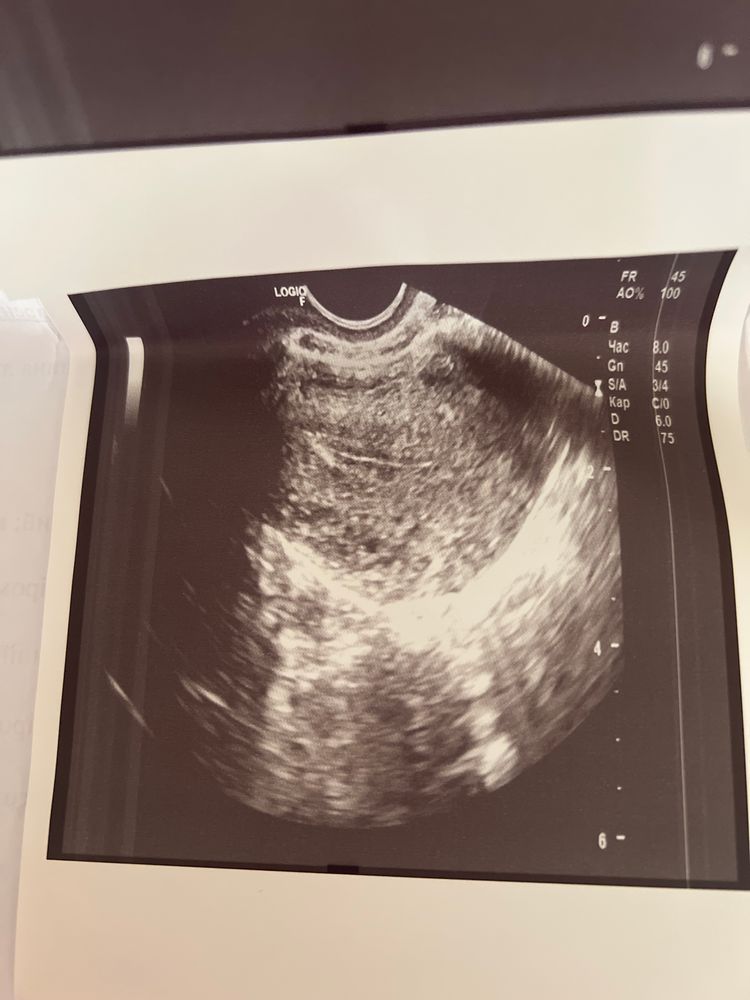

Была у узиста, напугал этот черный маленький круг , от врача я комментариев по поводу ухи не услышала , может ли быть беременность ?

В матке нет никакого кружка, это не беременность. Узист бы вам точно сказал, если бы нашел

Я была на узи планово после воспаления придатков, но о б не знала и врач не увидел, а на тот момент было 3 недели беременности, как оказалось. Не знаю, может это слишком маленький срок, чтобы хоть что-то увидеть